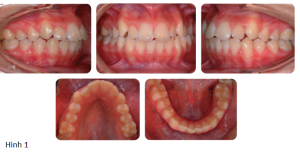

Bệnh nhân nữ 16 tuổi có sai khớp cắn hạng III trên nền xương hạng II nhẹ với tăng kích thước dọc phức tạp bởi chen chúc nhẹ và hô 2 hàm (Hình 1, Hình 2)